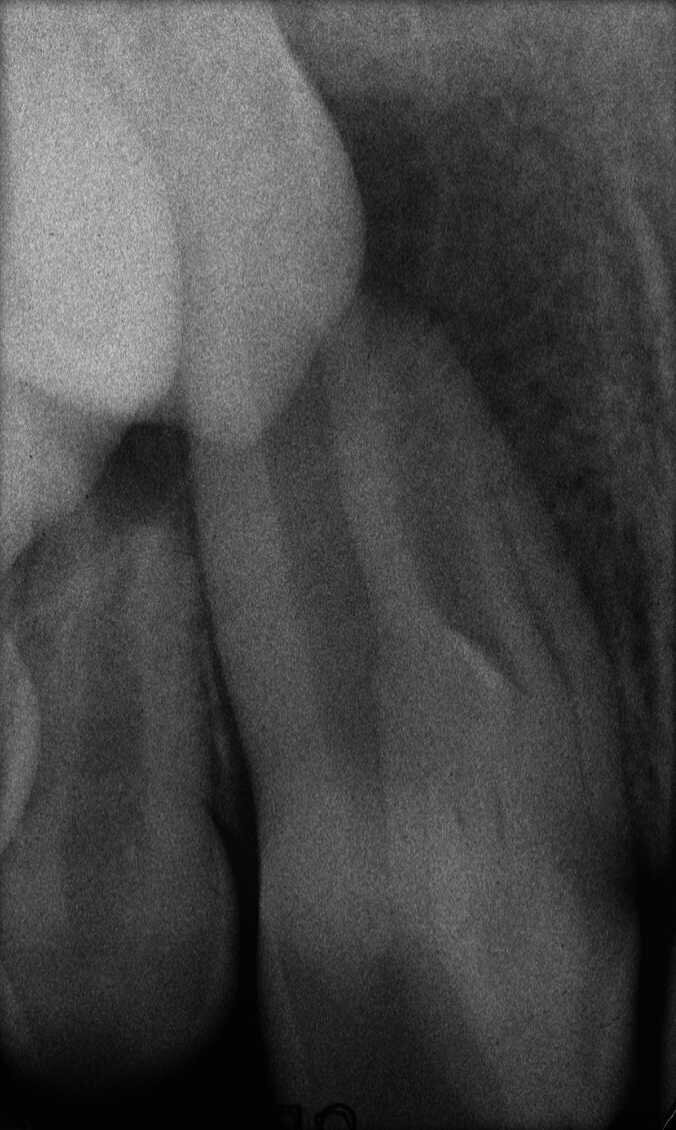

Dans la prémolaire maxillaire présentée dans les figures 5 et 6, le fistulogramme indique la présence d’une lésion apicale, qui s’étend en direction coronaire jusqu’au tiers moyen de la racine. La décision clinique pourrait donc s’orienter vers un retraitement orthograde ; toutefois, le cliché CBCT nous donne une tout autre vision de la situation que celle de la radiographie, dans la mesure où il montre une lésion irréversible de la dent due à un traitement antérieur, et la nécessité de l’extraire.